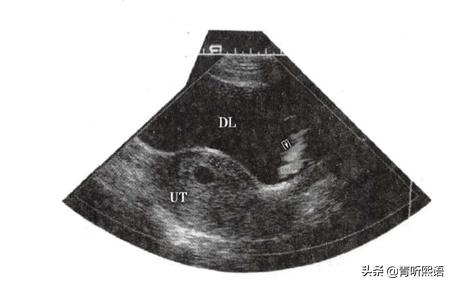

B超检查

妊娠早期超声检查不仅能确定胚胎在子宫内发育,还能确定胎数,排除宫外孕等情况。

- 一般停经35 日时,B超检查发现子宫腔内见到圆形或椭圆形妊娠囊,提示宫内早孕,建议一周后复查。

- 一般妊娠6周时, B超检查可见到胚芽和原始心管搏动,这就提示胚胎存活。